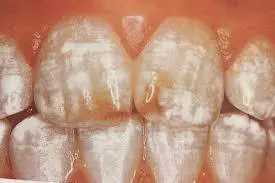

・歯の黄色環(カドミウムリング)